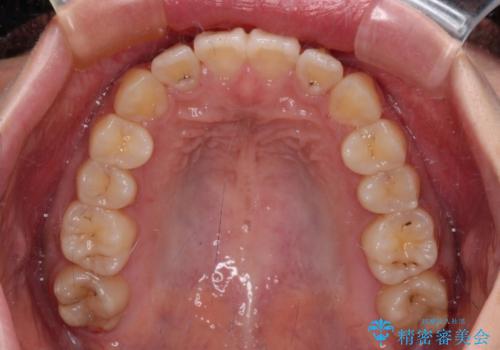

しっかりと装着時間を守ってくださったので、予定通り1年強で治療を終えることができました。

- 前歯の捻れを気にして来院された患者様です。

上顎前歯が捻れて前方に飛び出しており、下顎前歯もそれに沿うようにデコボコとなっていました。

IPR(歯と歯の間を削る処置)によりスペースを獲得して下顎前歯のデコボコを改善し、上顎前歯は下顎前歯と接する位置にまで引っ込めるように設定し、インビザラインにて矯正治療を行うこととしました。